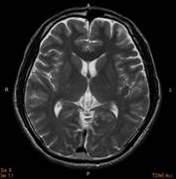

当院の脳ドックMRI画像

T2強調画像